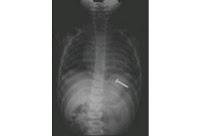

Caso 2

Como veo que les gusta, de vez en cuando, hacer de médicos de guardia aquí les pongo dos radiografías. Ustedes están de guardia un sábado de madrugada y se en cuentran frente a estas dos situaciones. En cada una de ellas me han de decir lo que ven, qué puede haber ocurrido y cómo "arreglamos" a estos angelitos. Ninguno de estos dos niños estaba en fermo pero uno de ellos tuvo que pasar por el quirófano. ¿Cuál y porqué?Suele ocurrir por descuido de los padres o de forma accidental pero el "trasiego" que pueden povocar es de órdago. Vigilen y estén atentos con sus vástagos; todo lo que entra por la boca...